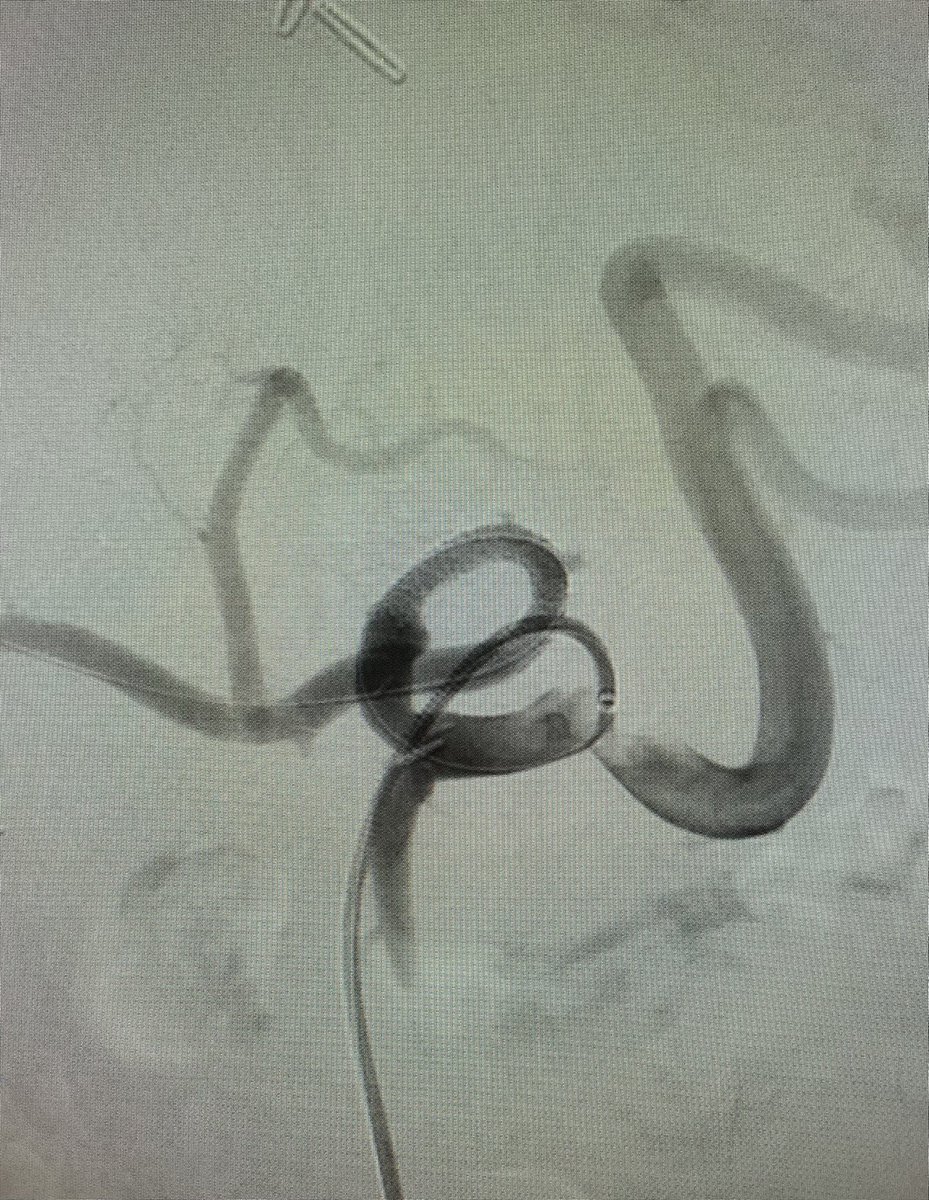

Massive hemoptysis in setting of PNA and anticoagulation. POSITIVE bleed seen from selective bronchial art run 🫁🩸👀. No more hemoptysis after bronchial art embo (BAE) w 300-500 micron particles. The Dotter Institute Ryan Schenning, MD SIR ECS SIR RFS

Massive hemoptysis in setting of PNA and anticoagulation. POSITIVE bleed seen from selective bronchial art run 🫁🩸👀. No more hemoptysis after bronchial art embo (BAE) w 300-500 micron particles. <a href="/dotter_IR/">The Dotter Institute</a> <a href="/Ryan_Schenning/">Ryan Schenning, MD</a> <a href="/SIR_ECS/">SIR ECS</a> <a href="/SIRRFS/">SIR RFS</a>